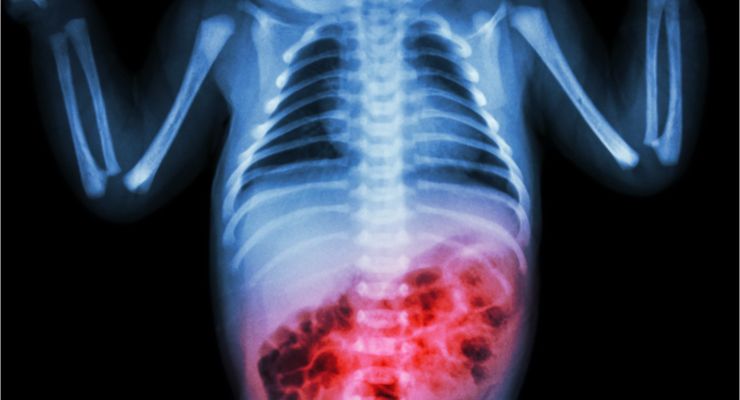

Breyts and Novac learned that Rowan had a condition that doctors called necrotizing enterocolitis (NEC). Rowan’s doctors explained that NEC is a serious disease where bacteria gets into the intestinal wall, which then leads to small holes in the intestines.

Once the intestines are perforated, waste and bacteria then begin to leak into the abdomen, which causes deadly infections. The couple learned that NEC is typically seen in babies and most often occurs in infants like Rowan that are born prematurely.